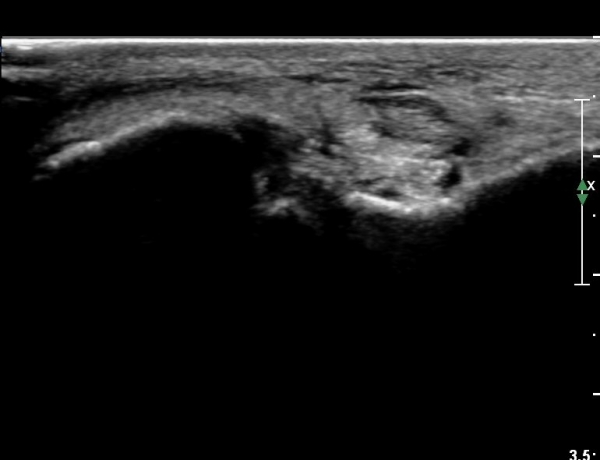

Á¾°ñºñ°ñÀδë Á¾´Ü¸é°Ë»ç¿¡¼­ ƯÀÌ ¼Ò°ßÀ» º¸ÀÌÁö ¾Ê´Â´Ù(»çÁø 6, 7).